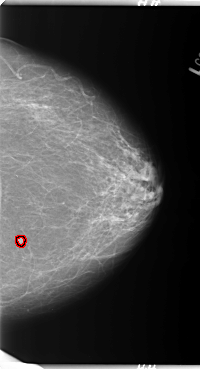

B_3089_1.LEFT_MLO

LEFT_MLO LINES 5952 PIXELS_PER_LINE 3352 BITS_PER_PIXEL 12 RESOLUTION 50 OVERLAY

FILE: B_3089_1.LEFT_MLO.OVERLAY

TOTAL_ABNORMALITIES 1

ABNORMALITY 1

LESION_TYPE MASS SHAPE ROUND MARGINS ILL_DEFINED

ASSESSMENT 4

SUBTLETY 4

PATHOLOGY MALIGNANT

TOTAL_OUTLINES 1

BOUNDARY